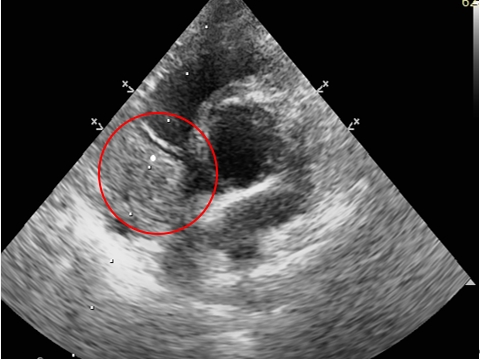

胸腔x光評估胸腔有無團塊,心臟大小;如果有心包囊積液,心臟會呈現圓且大的型態 (球形)。心臟超音波下評估心臟功能,心臟內外有無團塊樣組織,有無心包囊積液。

紅色圈為心臟超音波下,右心房內團塊